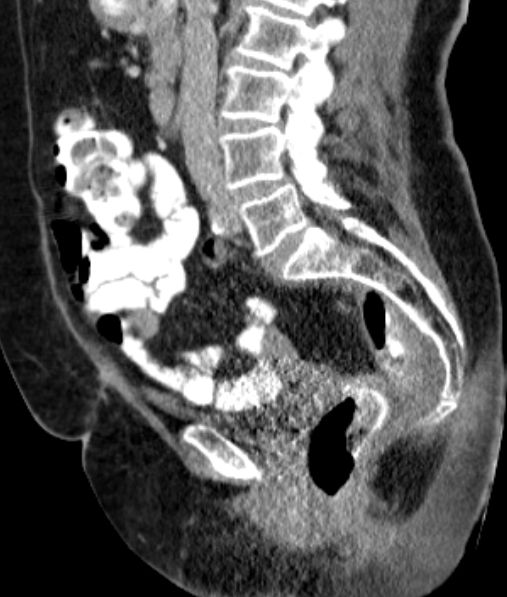

endoskopische, mikrochirurgische Abtragung 72-jährige Frau 6 Wochen nach laparoskopischer OP eines Rektumkarzinoms bei 9 cm ab ano. Rektal tastet man eine prall elastische stark druckdolente Resistenz. Das CT zeigt eine Nahtinsuffizienz mit KM-Austritt, Gasblase und präsakralem Abszess